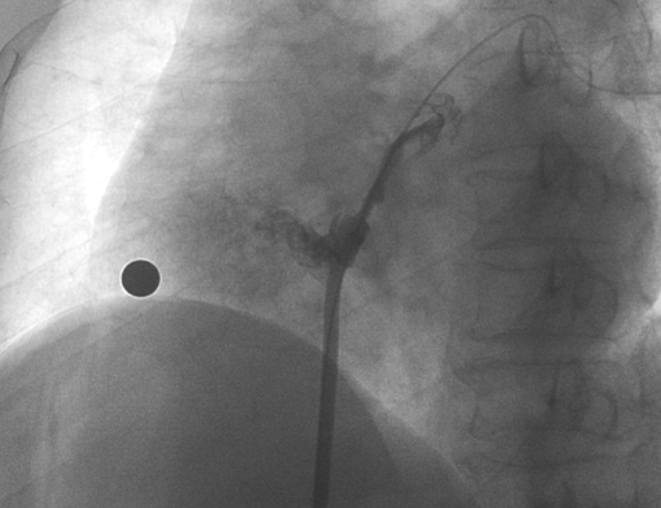

術(shù)中造影顯示患者為PFO且長隧道型,目前市場上已商業(yè)化的PFO封堵器難以滿足該患者解剖結(jié)構(gòu)封堵需求。迪創(chuàng)醫(yī)療自主研發(fā)的OmniSeal PFO封堵器自適應性雙盤貼合設(shè)計能廣泛適應不同PFO隧道長度的解剖結(jié)構(gòu)和形態(tài),其雙盤外包覆式阻流和隧道內(nèi)填充阻流相結(jié)合的雙重阻流設(shè)計,可為此患者實現(xiàn)有效封堵。與此同時,OmniSeal首創(chuàng)的完全可穿刺式設(shè)計,也為此患者最大程度地保留了房間隔區(qū)域穿刺通道,以實現(xiàn)全兼容未來可能的左心系統(tǒng)二次介入術(shù)。術(shù)終造影和心臟超聲顯示封堵完全、效果良好。作為OmniSeal的首例臨床應用,本次手術(shù)的順利完成和優(yōu)異效果充分體現(xiàn)了產(chǎn)品的設(shè)計創(chuàng)新優(yōu)勢。

造影顯示長隧道型PFO